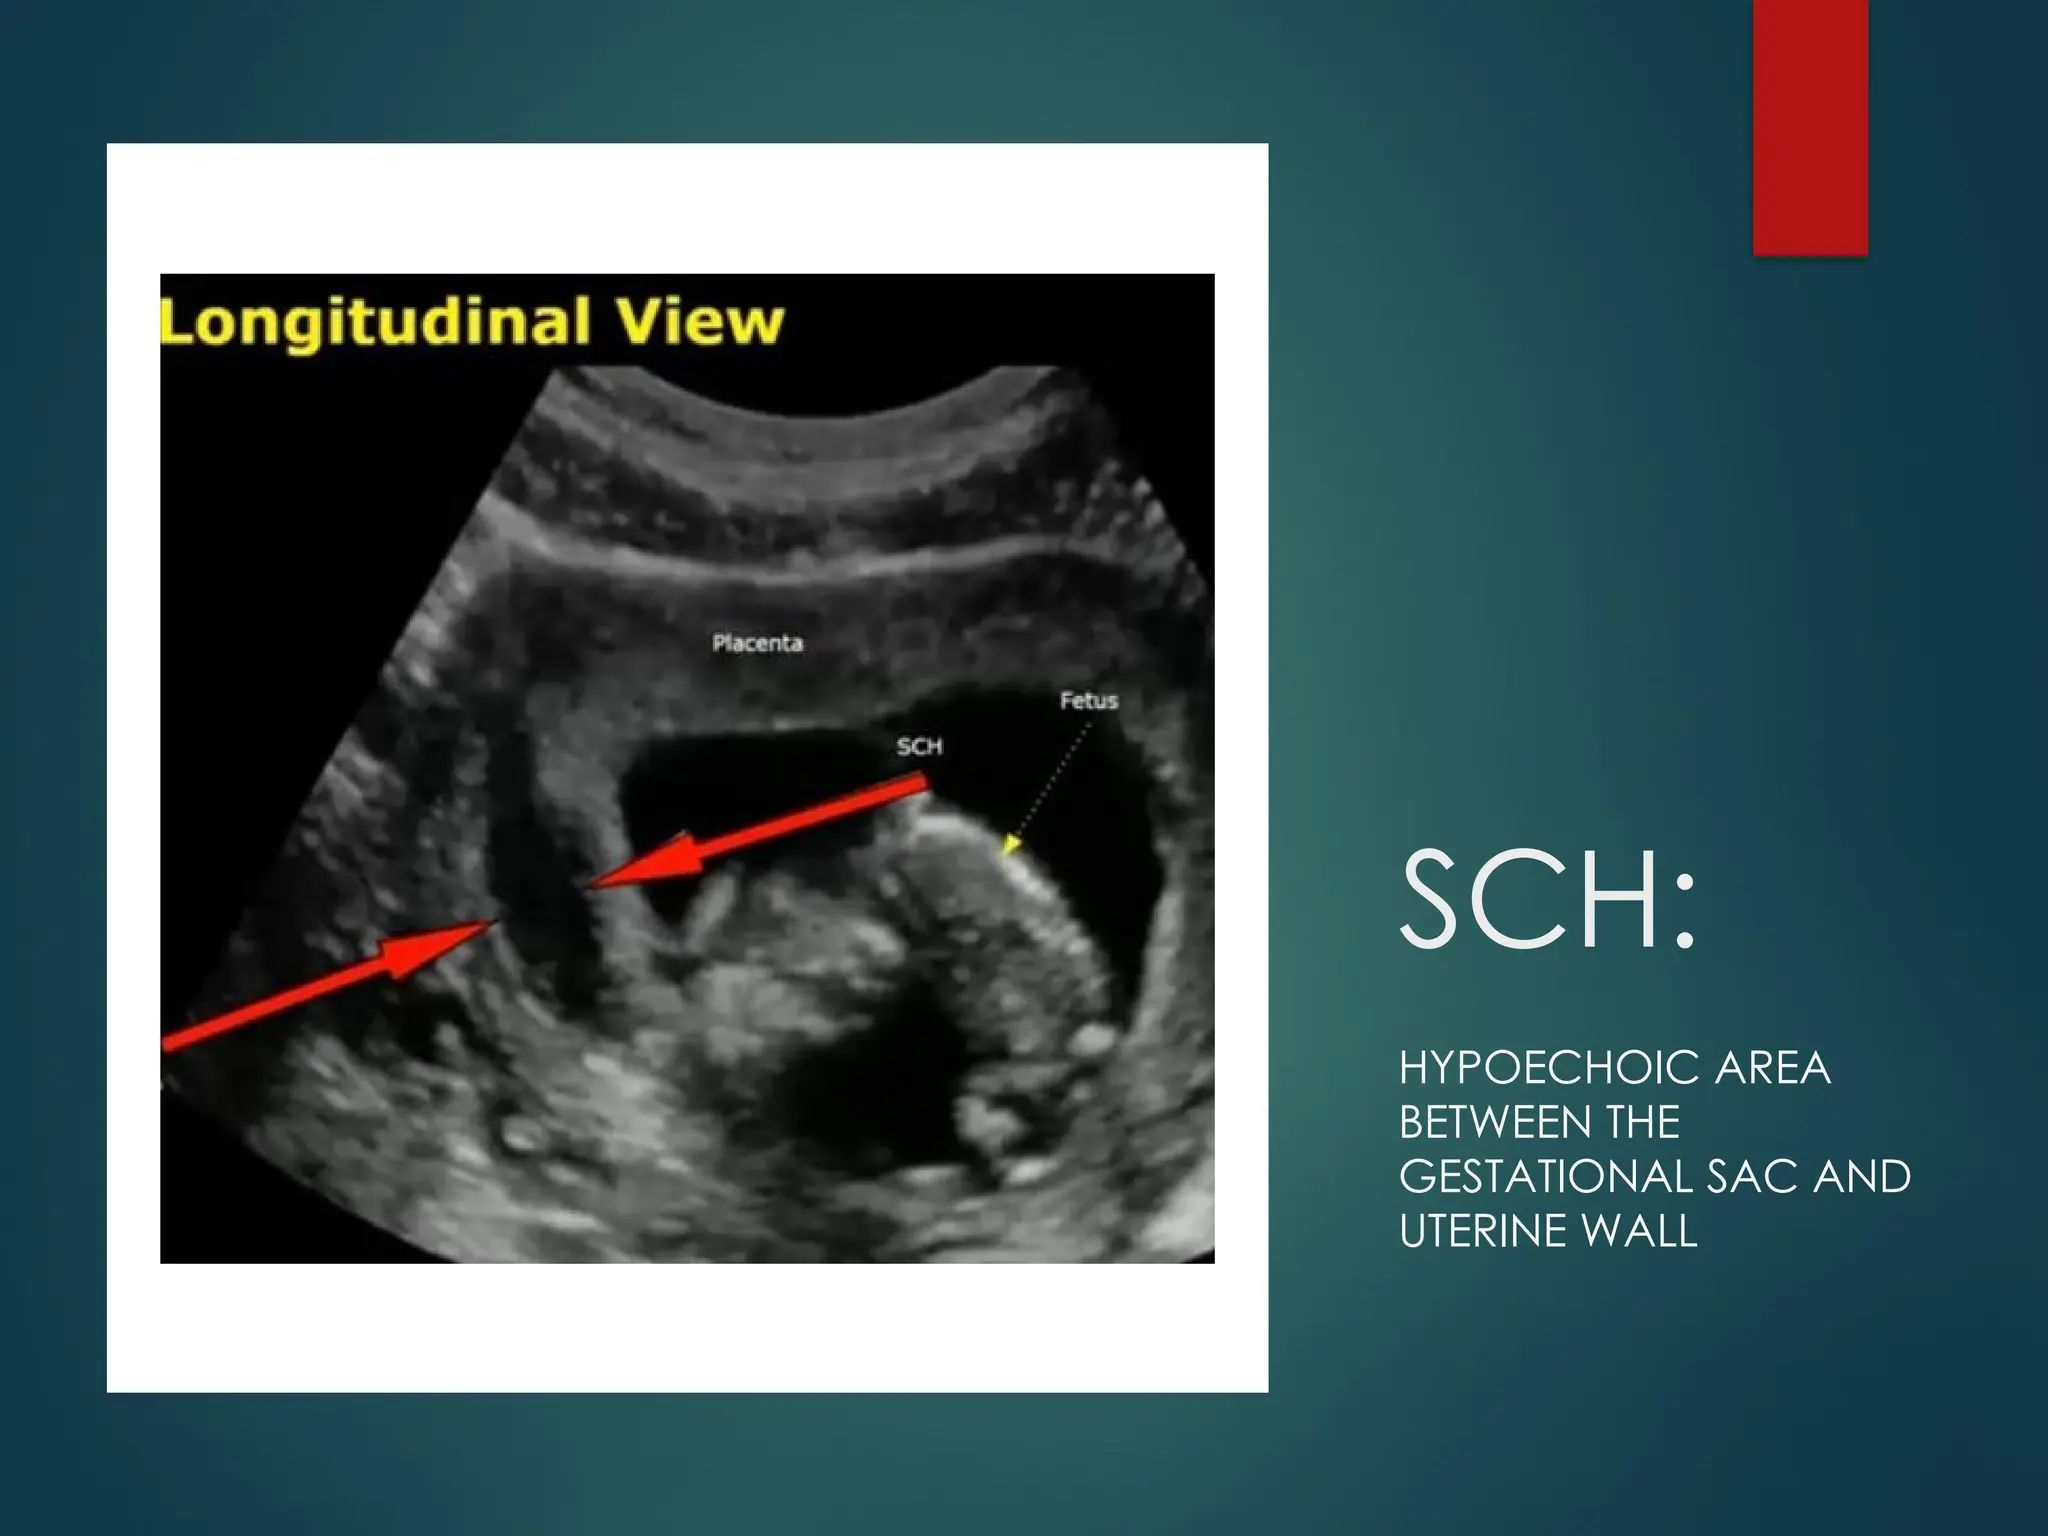

SCH:

HYPOECHOIC AREA

BETWEEN THE

GESTATIONAL SAC AND

UTERINE WALL

Grading of

Subchorionic

Haemorrhaage:

SMALL: <20% of the size of

gestational sac

Medium: 20-50% of the size of

Large: >50% of the size of

gestational sac (higher risk of

complications such as

miscarriage)

Grading of Subchorionic Haemorrhaage: SMALL: <20%of the size of gestational sac Medium: 20-50% of the size of gestational sac Large: >50% of the size of gestational sac (higher risk of complications such as miscarriage)

HYPOECHOIC CRESCENT SHAPEDFLUID COLLECTION ADJACENT TO THE GESTATIONAL SAC